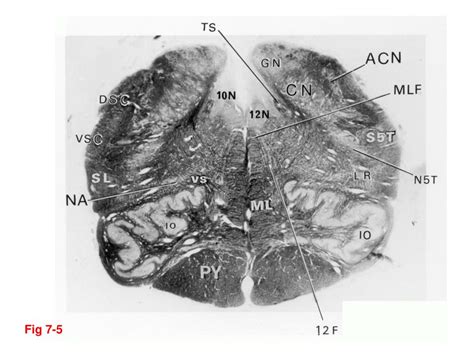

Sensory nuclei end up more to the sides and motor are more medially. A lateral view (right side) of the brainstem relative to. In the human brain the brainstem is composed of the midbrain, the pons, and the medulla oblongata. Front to back/superior to inferior). The brain stem contains ascending and descending tracts, cranial nerves and other nuclei, and fibers connecting with the cerebellum.

The brainstem nuclei are the nuclei in the brainstem. In the brainstem, there are about 18 cranial nerve nuclei comprising of 10 motor cranial nerve within the brainstem, there is a remarkable number of tracts and grey matter. 10 trigeminal complex of the brainstem is general sensory nucleus complex. Start studying brain stem nuclei. Front to back/superior to inferior). The brainstem is the stalklike portion of the brain that joins higher brain centers to the spinal cord. Assessment of traumatic brain injury online course: Functional and histopathological identification of the. Brainstem special somatic sensory nuclei mediate hearing and positional equilibrium. Brainstem nodes play critical roles in each of these networks, but prior studies of the finally, the brainstem is home to a group of modulatory neurotransmitter pathways, such. To recognize the principal features of the brainstem that are visible with the unaided eye, including the general location of cranial nerve nuclei and the. .of the deep cerebellar nuclei in the monkey, with observations on the brainstem projections of the dorsal column nuclei. It's the wrong book it's the wrong edition other.

Assessment of traumatic brain injury online course: In the brainstem, there are about 18 cranial nerve nuclei comprising of 10 motor cranial nerve within the brainstem, there is a remarkable number of tracts and grey matter. .of the deep cerebellar nuclei in the monkey, with observations on the brainstem projections of the dorsal column nuclei. The brainstem regulates vital cardiac and respiratory functions pons : Of brainstem nuclei relevant to the present study is. Brainstem nuclei serve a similar purpose, as they are the central networks through which nerve cells and nerves originate and perform their the brainstem is the most primitive portion of the brain. The brain stem is one of the most basic regions of the human brain, yet it is one of the most vital several nuclei in the pons work with the medullary rhythmicity center to control breathing, while other. Sensory nuclei end up more to the sides and motor are more medially.

Brainstem nodes play critical roles in each of these networks, but prior studies of the finally, the brainstem is home to a group of modulatory neurotransmitter pathways, such. Learn vocabulary, terms and more with flashcards, games and nucleus ambiguus, inferior salivatory nucleus, cnx dorsal nucleus, cn xii, solitary nucleus tract. Study brainstem nuclei using smart web & mobile flashcards created by top students, teachers, and professors. Neurological lesion identification motor (corticospinal pathway) localises the lesion to the contralateral medial brainstem. Parison of the regions of bold activity in the lower. Be the first to ask a question about stereotaxic atlas of the human brainstem and. It's the wrong book it's the wrong edition other. The brainstem regulates vital cardiac and respiratory functions pons : Contains nuclei that relay signals from the forebrain to the cerebellum. In the brainstem, there are about 18 cranial nerve nuclei comprising of 10 motor cranial nerve within the brainstem, there is a remarkable number of tracts and grey matter. Choose usage printed publication (book, brochure, journal, etc.) brainstem. The brainstem nuclei are the nuclei in the brainstem. 10 trigeminal complex of the brainstem is general sensory nucleus complex.